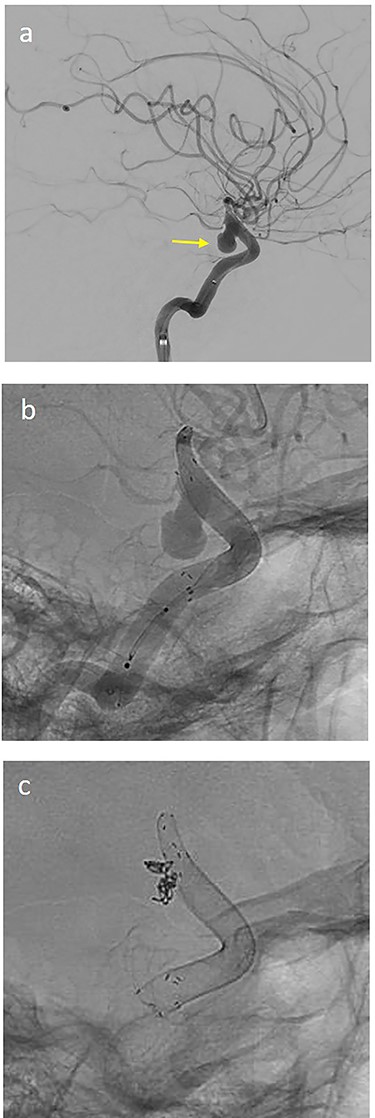

On the next day (Day 9 post-op), the patient suffered from acute and devastating headaches, with screaming and enuresis. An emergency computed tomography (CT) was carried out and displayed a prepontine and retroclival subarachnoid hemorrhage (Hunt & Hess Grade I), (Fig. 2). For further evaluation, a digital subtraction angiography (DSA) was conducted, and it showed a pseudoaneurysm of ophthalmic1/supraclinoid2/C23 part of the left ICA, which was directly treated by a flow diverter (Derivo®—4,5/20), with remaining rest flow (Fig. 3). The patient was transferred to the ICU, transcranial doppler sonography was performed and revealed normal flow. In the following course, the patient suffered from Terson’s syndrome and hyponatremia due to SIADH, but after clinical improvement, was transferred back to normal station after 10 days of post-operative monitoring. Furthermore, the patient was plagued with cephalgia and nausea, which could not be compensated with analgetics and antiemetics. On the 20th post-operative day after the epileptic seizure with postictal vigilance reduction, an emergency CTA was conducted showing progressive SAH (Fig. 4) and a growing pseudoaneurysm as well as generalized vasospasm with posthemorrhagic hydrocephalus. For an emergency CSF diversion, an external ventricle drain was placed. The repeated DSA showed a growing false aneurysm which was treated with two additional flow diverters (2× Derivo®—4,5/20) as well as coiling (HydroSoft™ 2/3 and 2× 1,5/2) by endoleak (Fig. 5). The vasospasms were treated by an intraarterial spasmolysis (Fig. 6).

(a) lateral angiogram of left carotid artery showing ICA aneurysm before the second endovascular treatment; (b) Lateral view after implantation of two additional flow diverters (2× Derivo®—4,5/20); (c) Lateral view after additional coil embolization (HydroSoft™ 2/3 and 2× 1,5/2).